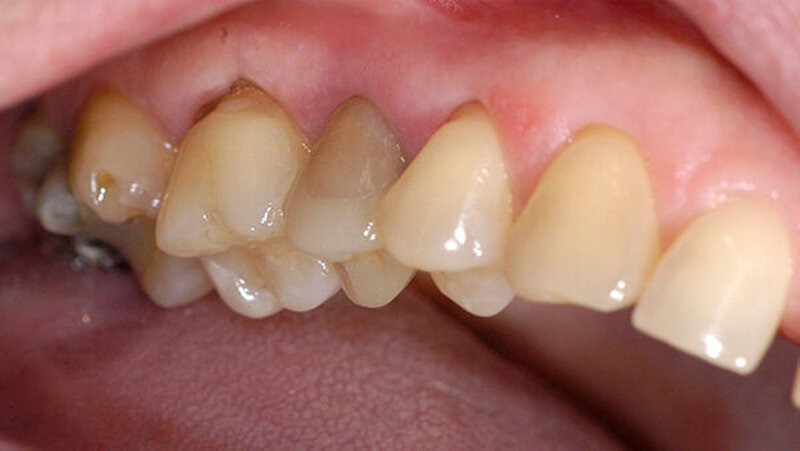

Nachdem die Patientin darüber aufgeklärt wurde, wie der Zahn möglicherweise erhalten werden kann, wurden die Zahnfragmente nach Gabe einer Infiltrationsanästhesie schonend extrahiert (Abbildung 3). Nach der Extraktion wurden die zwei Zahnfragmente zunächst in der Zellnährlösung einer Zahnrettungsbox (Medice Pharma, Iserlohn) geschwenkt, um sie von Blut und Gewebe zu säubern. Das apikale Granulationsgewebe, das bei der Extraktion an der Wurzelspitze verblieben war, konnte manuell mit einer Luer Zange entfernt werden.